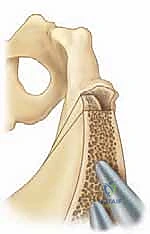

الهدف من جراحة سالتر ليس تغيير شكل التجويف نفسه (لأنه يكون قد اكتسب شكلاً كروياً جيداً)، بل الهدف هو "إعادة توجيه" (Redirection) هذا التجويف بأكمله. يتم ذلك عن طريق إجراء قطع عرضي كامل في عظم الحرقفة (Ilium) فوق مفصل الورك، ثم إمالة الجزء السفلي من الحوض (الذي يحتوي على التجويف) إلى الأسفل والخارج، ليغطي رأس عظمة الفخذ كالمظلة.

- إعادة التوجيه ووضع الطعم العظمي: يتم إمالة التجويف الحُقي للأسفل والأمام. وللحفاظ على هذا الوضع الجديد، يتم أخذ قطعة عظمية مثلثة الشكل (طعم عظمي - Bone Graft) من الجزء العلوي من عظم الحوض، ويتم حشرها في مساحة القطع العظمي كـ "وتد".